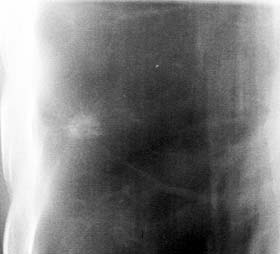

Рис. 3. Плоскоклеточный рак. Дополнительная тень неоднородной структуры с неровными, нечеткими мелкозазубренными контурами. Цифровая томограмма.